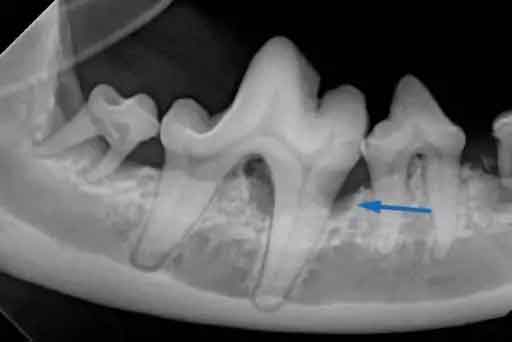

Pets in Coomera can rest assured that we place their dental health at top priority! Foxwell vets use the latest in dental health techniques, and can utilise X-ray and blood tests to ascertain exactly what is going on in your pet’s mouth.

Because we can’t ask your pet to “open wide” we utilise a general anaesthetic to allow us to assess, and clean, their teeth and gums thoroughly. If we encounter severely diseased teeth, it is best practice to remove these to cease pain for your pet, and to limit the possibility of further infection.